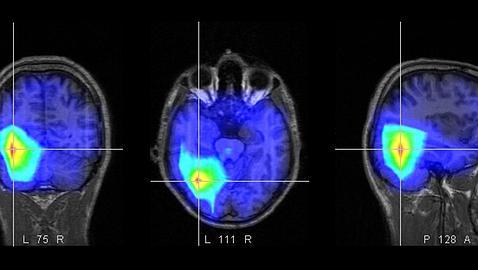

El pasado agosto, el norteamericano Nicholas Carr, ex editor ejecutivo de la Harvard Business Review y un famoso escritor especializado en tecnología, aseguraba en su libro «The Shallows», que internet, pese a sus múltiples ventajas, tiene un peligroso efecto sobre nuestros cerebros. A su juicio, la sociedad digital está alterando nuestra capacidad de reflexión y de aprendizaje, de forma que el cerebro no es capaz de profundizar ni de prestar la atención necesaria. En definitiva, nos vuelve más estúpidos.

Nicholas Carr afirma en la revista «Esquire» que la tecnología nos ha convertido en unos adictos y nos ha provocado una regresión a un estado no más sofistificado que el de una rata de laboratorio. ¿Cuántas veces miramos al día nuestro correo electrónico? Un estudio dice que en las oficinas británicas los trabajadores lo hacen 30 veces a la hora. Por cada nuevo mensaje, nuestro cerebro libera una dosis de dopamina, una sustancia química que induce al placer y que se ha relacionado con los comportamientos adictivos.

Carr considera que la abundancia de información de la era digital «dificulta el pensamiento profundo, la comprensión y la formación de recuerdos». Además, hace el aprendizaje más difícil y consigue que nuestra memoria sea más pobre y dispersa.